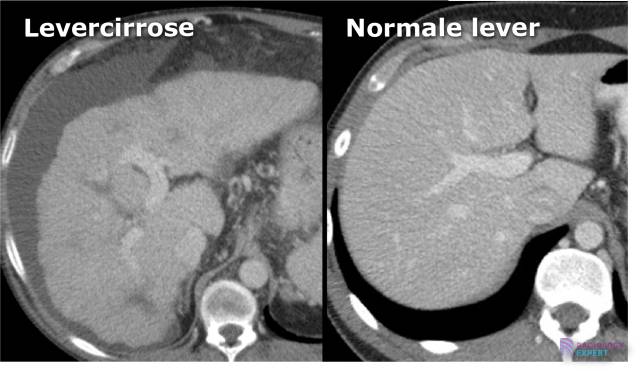

Levercirrose op een CT abdomen onderzoek Levercirrose op een CT abdomen onderzoek

• Levercirrose